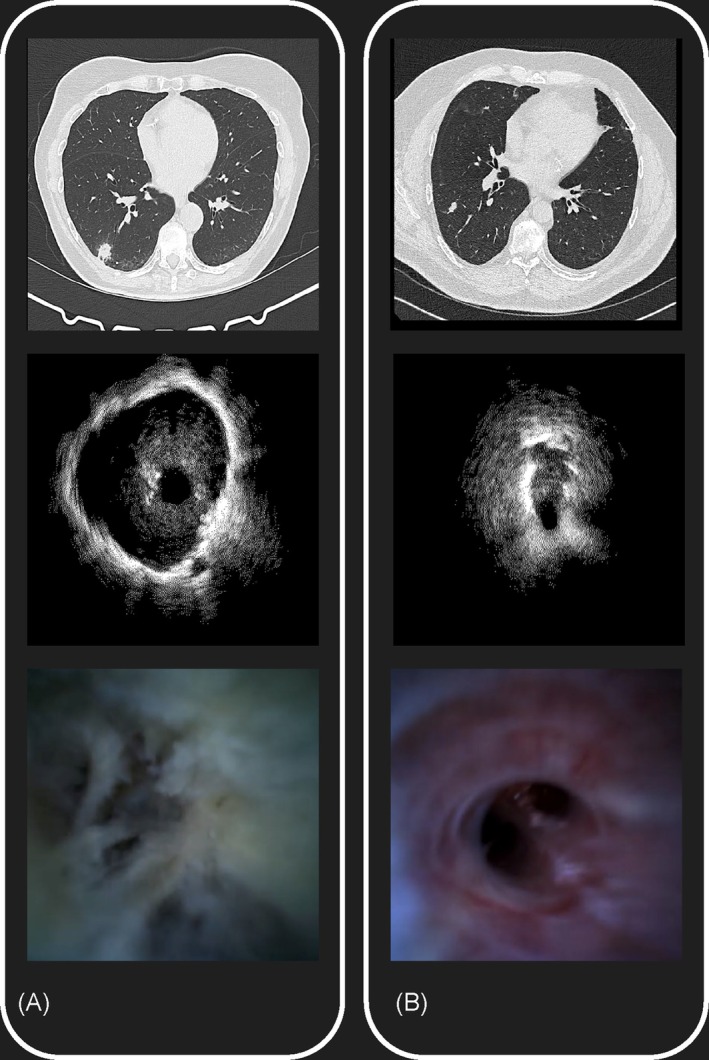

Background and objective: Iriscope, a 1.3 mm video endoscopic probe introduced through an r-EBUS catheter, allows for the direct visualisation of small peripheral pulmonary nodules (PPNs). This study assessed the ability of physicians with different levels of experience in bronchoscopy, and the ability of artificial intelligence (AI) to predict the malignant nature of small PPNs during Iriscope peripheral endoscopy.

Methods: Patients undergoing bronchoscopy with r-EBUS and Iriscope for peripheral PPNs < 20 mm with a definite diagnosis were analysed. Senior and Junior physicians independently interpreted video-recorded Iriscope sequences, classifying them as tumoral (malignant) or non-tumoral, blind to the final diagnosis. A deep learning (DL) model was also trained on Iriscope images and tested on a different set of patients for comparison with human interpretation. Diagnostic accuracy, sensitivity, specificity, and F1 score were calculated.

Results: Sixty-one patients with small PPNs (median size 15 mm, IQR: 11-20 mm) were included. The technique allowed for the direct visualisation of the lesions in all cases. The final diagnosis was cancer for 37 cases and a benign lesion in 24 cases. Senior physicians outperformed junior physicians in recognising tumoral Iriscope images, with a balanced accuracy of 85.4% versus 66.7%, respectively, when compared with the final diagnosis. The DL model outperformed junior physicians with a balanced accuracy of 71.5% but was not superior to senior physicians.

Conclusion: Iriscope could be a valuable tool in PPNs management, especially for experienced operators. Applied to Iriscope images, DL could enhance overall performance of less experienced physicians in diagnosing malignancy.